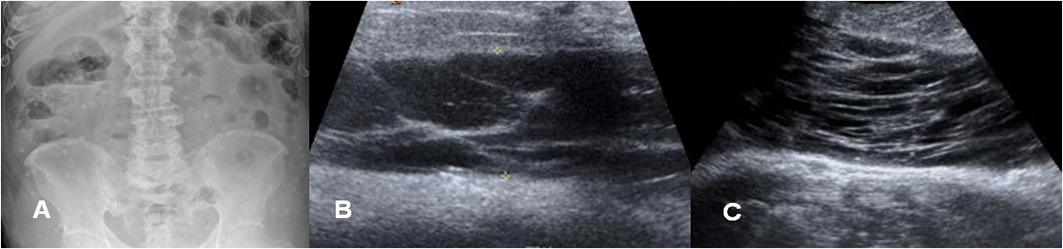

Fig 207 A. Seroma.

A: Rx AP. Paciente con múltiples cirugías abdominales, a la que se le colocó una malla abdominal.

B y C: Ecografías. En el PostQx aparecen cambios inflamatorios en la cicatriz Qx y se identifica colección líquida, con ecos y septos en su interior, que corresponde a seroma.